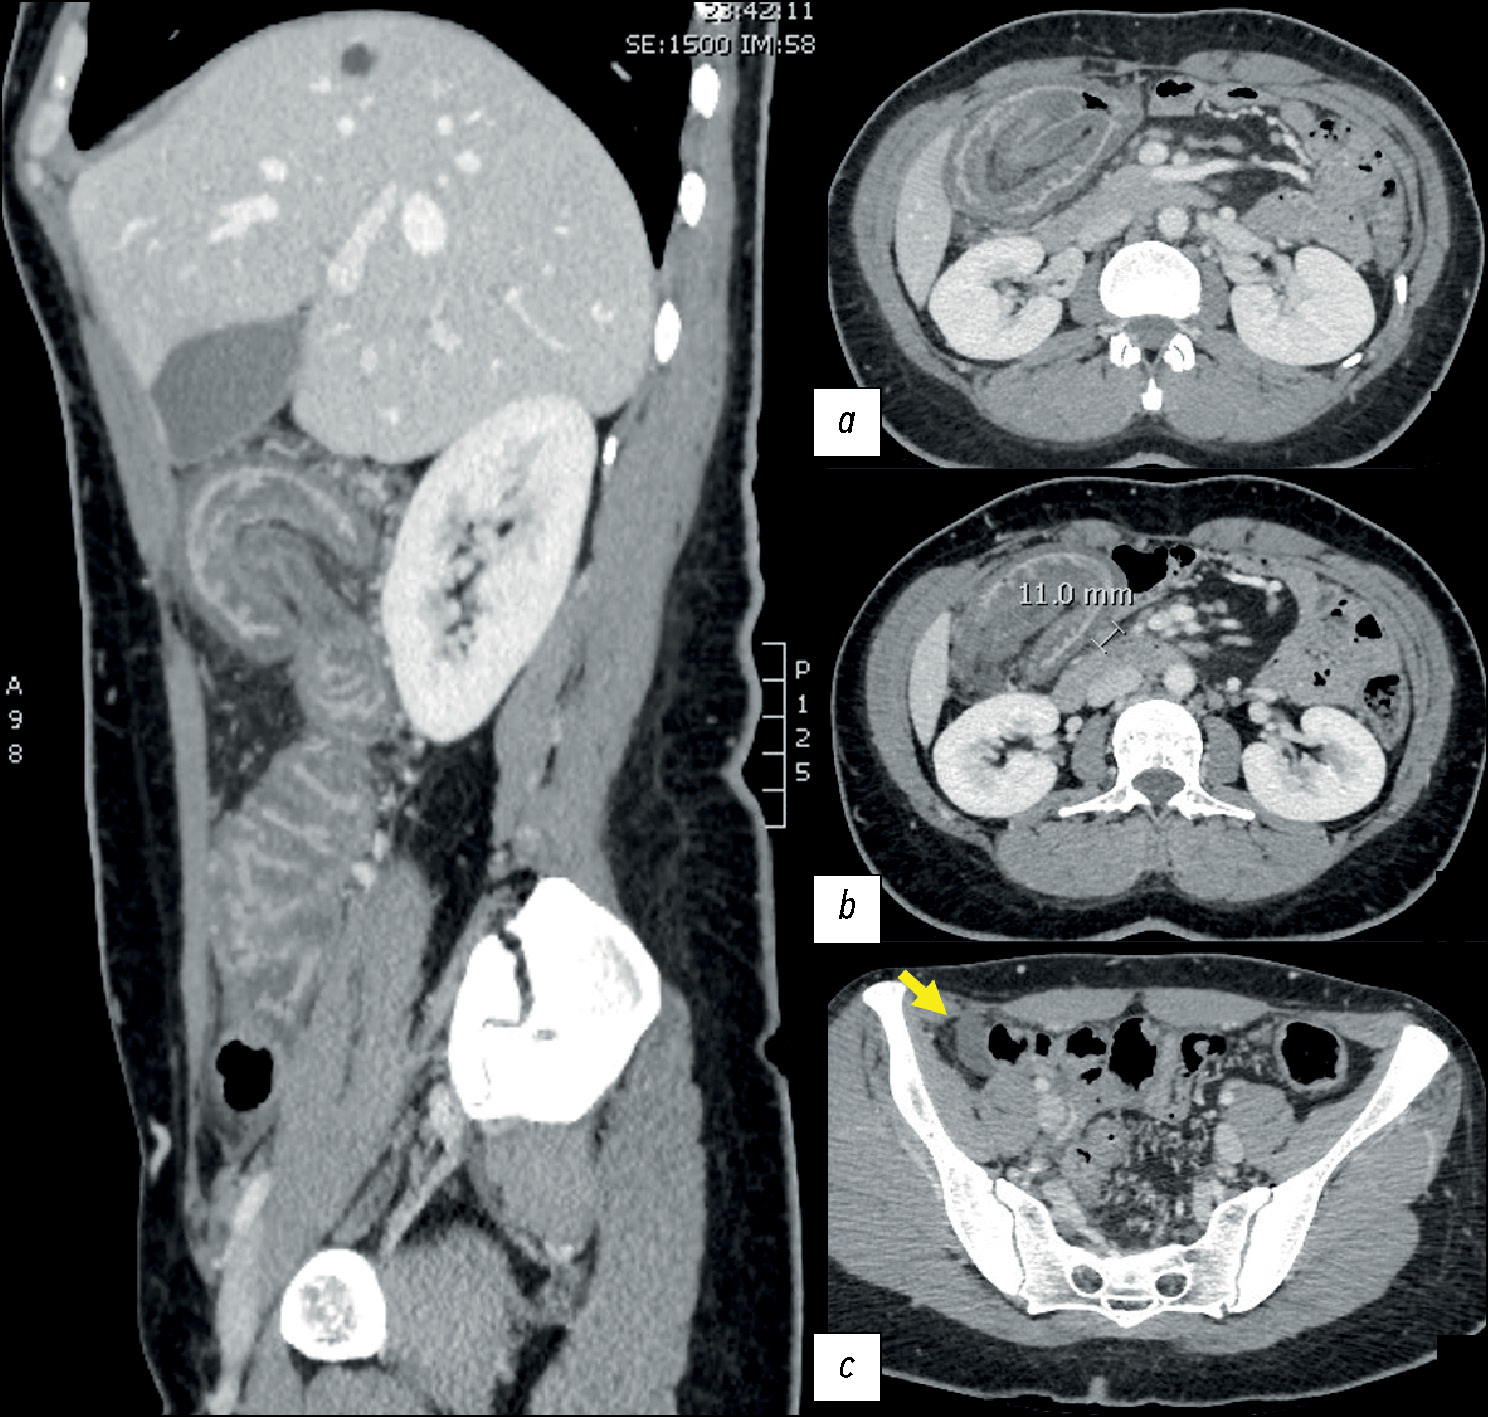

Difficulties in the radiological diagnosis of mature adrenal teratoma mimicking neuroblastoma in a child

Abstract

The most common adrenal tumor in young children is neuroblastoma, which can be difficult to differentiate from other conditions such as nephroblastoma, adrenal hemorrhage, angiomyolipoma, myelolipoma, and adenoma. This article describes a case of teratoma, one of the rarest adrenal tumors in children. Initially, despite its large size, it demonstrated all the radiological and histological signs of neuroblastoma. Teratomas are germ cell tumors usually found in the gonads. Adrenal teratomas are extremely rare, accounting for approximately 0.13% of all adrenal tumors. Typically, adrenal teratomas are asymptomatic, as the retroperitoneal space is large enough to accommodate the growth of the tumor without causing symptoms. For the first time in domestic literature, we present a clinical case of adrenal teratoma in a 3-month-old child. The article also presents a detailed description of the diagnostic process and challenges that radiologists and clinicians face when encountering a common tumor in a very rare location for children. This report aimed to help physicians increase awareness of this rare condition and include adrenal teratomas in the potential differential diagnosis of adrenal neoplasms.